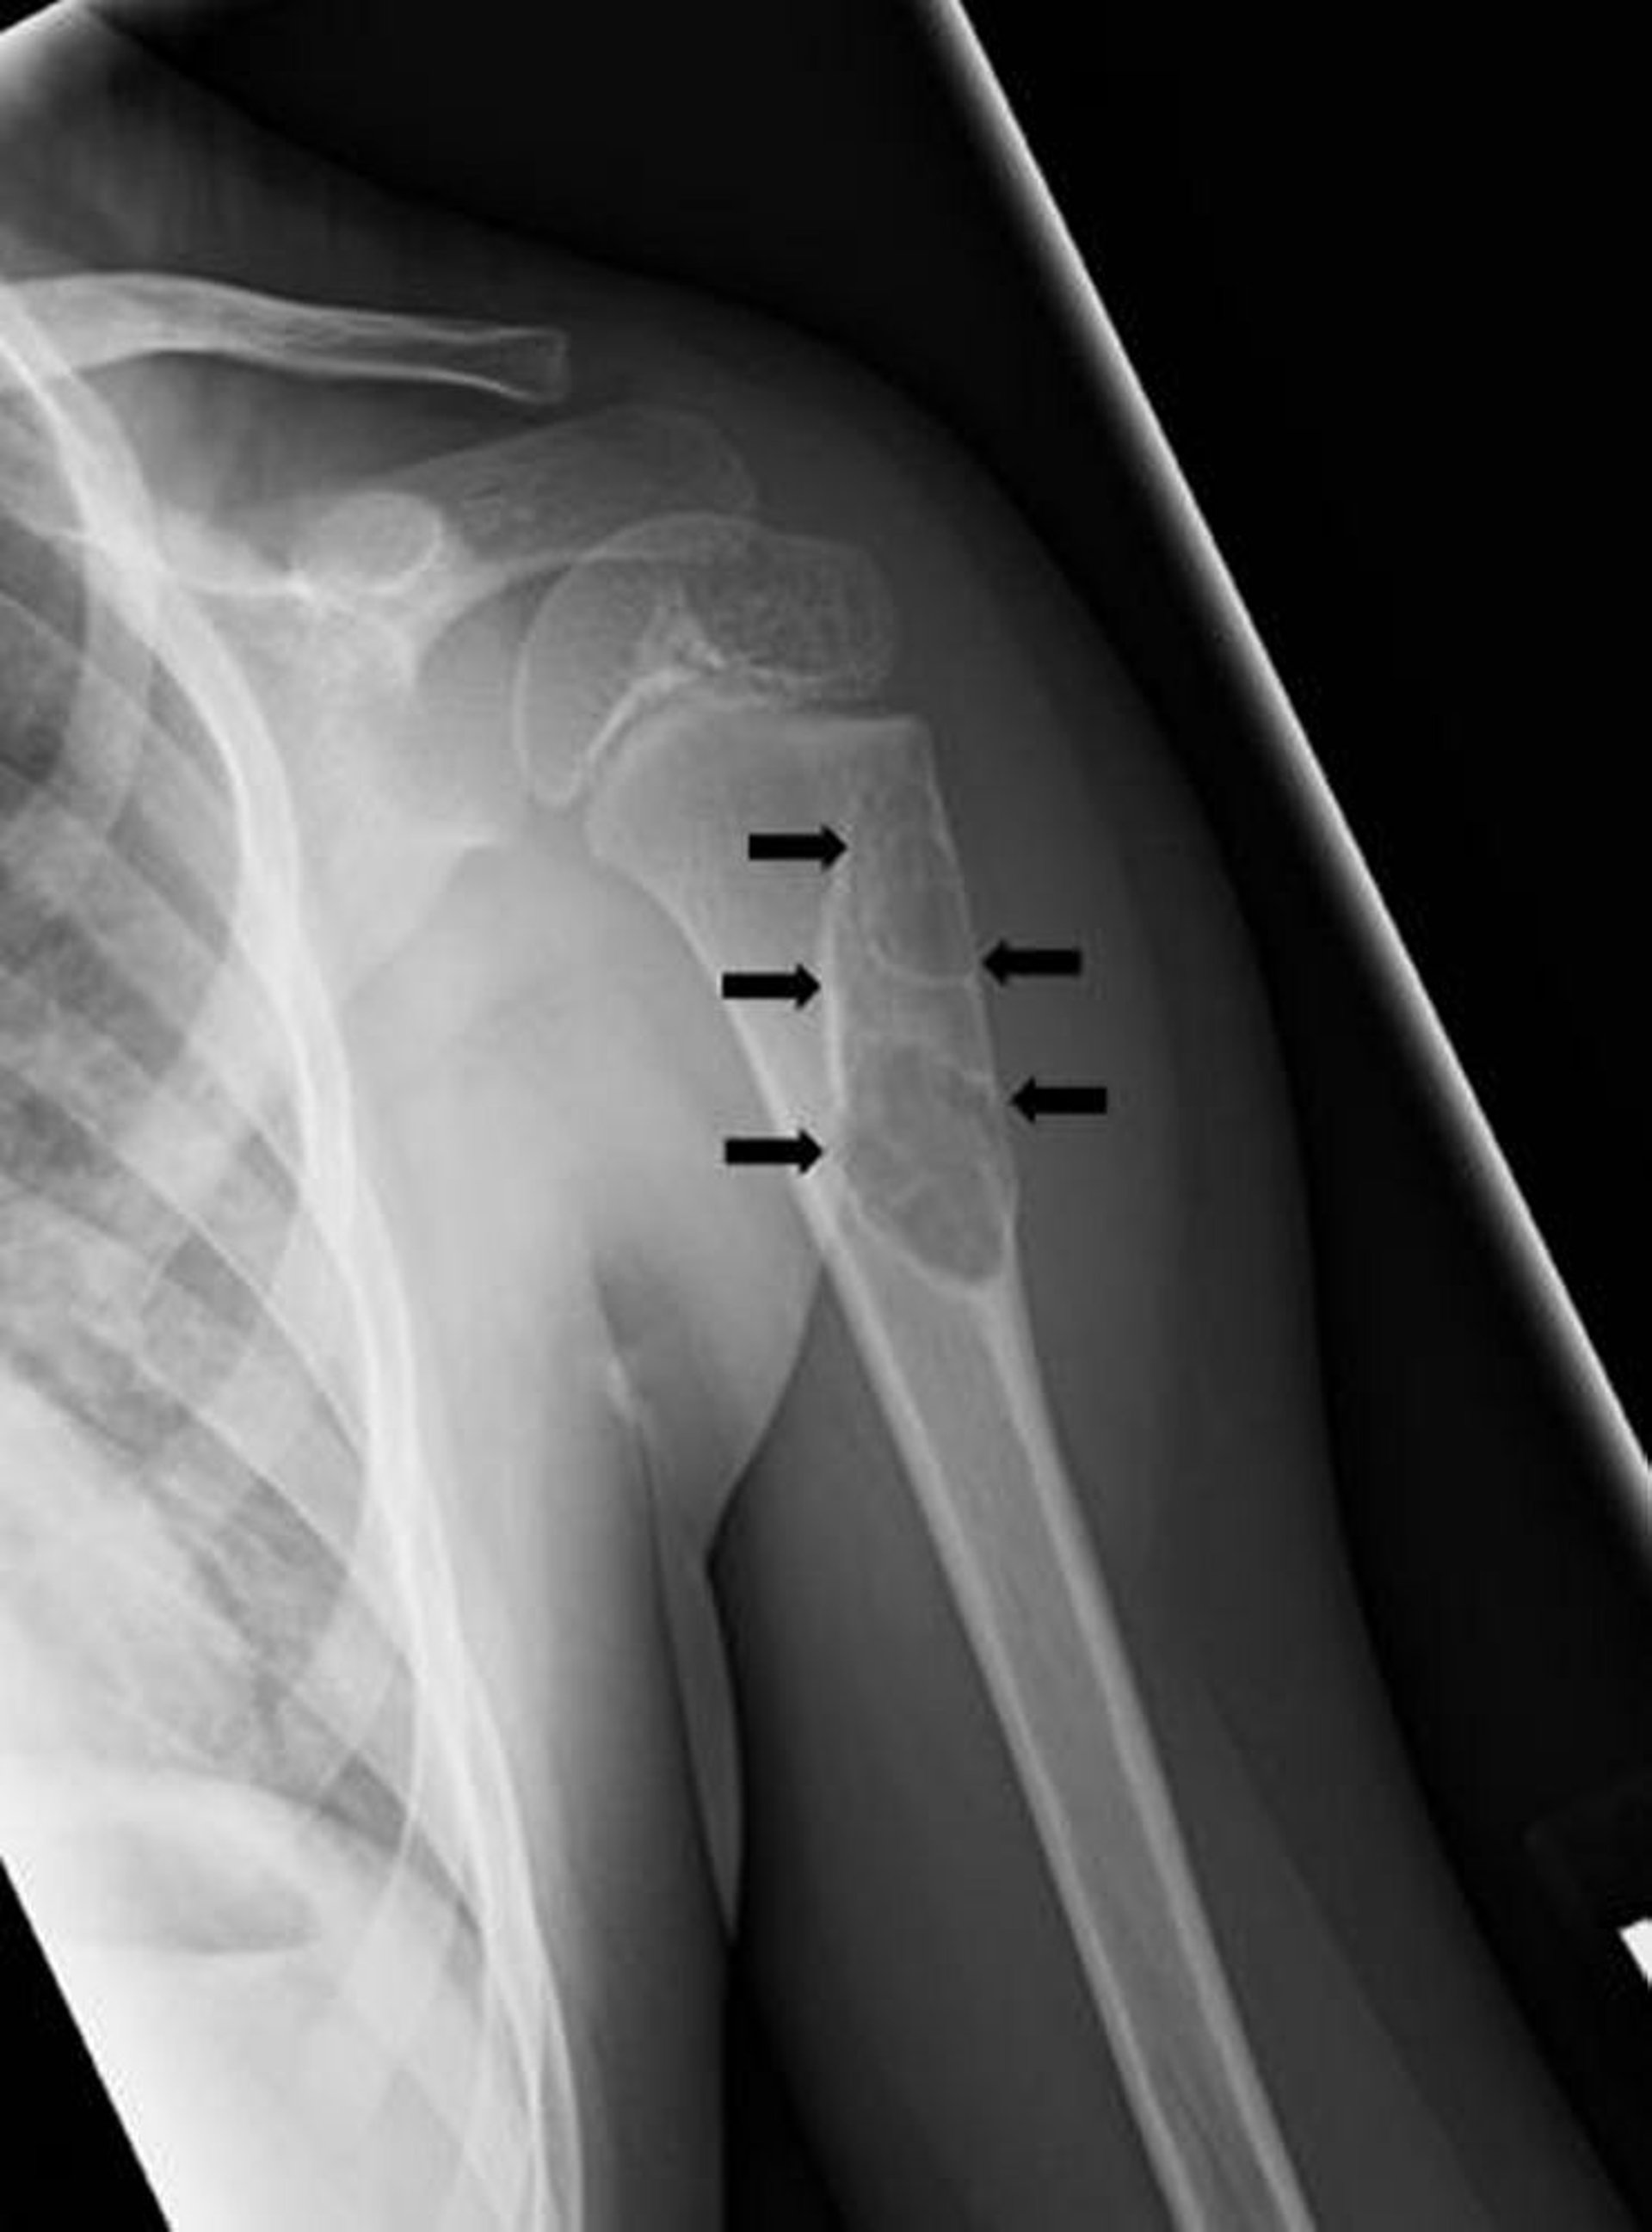

Quiste óseo unicameral

Esta radiografía muestra un quiste óseo unicameral simple (flechas) en el hueso de la parte superior del brazo.

Imagen cortesía de Michael J. Joyce, MD, y Hakan Ilaslan, MD.